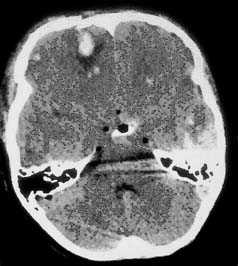

Компьютерная томография при травматическом повреждении головного мозга.

Применение компьютерной томографии в нейротравматологии существенно изменило представление о возможностях диагностики различных черепно-мозговых повреждений. КТ является в настоящий момент «золотым стандартом» - наиболее информативным методом обследования больных с черепно-мозговыми травмами и позволяет в самые короткие сроки судить о механизмах возникновения поражения мозга, его характере, распространенности, выраженности отека и дислокации мозга, а также динамике этих изменений.

КТ позволяет последовательно изучить мягкие ткани головы, кости черепа, вещество мозга, эпидуральные, субдуральные, субарахноидальные пространства, цистерны основания и желудочки мозга:

- выявить переломы свода и основания черепа (с чувствительностью, намного превышающей традиционную рентгенографию) ,

- выявить наличие внутричерепной гематомы (её характер, локализацию, размеры),

- выявить наличие очага ушиба головного мозга (его локализацию, размеры, характер, наличие геморрагического компонента),

- определить степень сдавления или дислокации головного мозга объемным процессом,

- выявить наличие диффузного или перифокального отека и его степени,

- выявить субарахноидальное кровоизлияние,

- выявить внутрижелудочковую гематому,

- выявить наличие пневмоцефалии.

Визуализация минимальных количеств излившейся свежей крови, уверенная дифференциация ее от других внеклеточных жидкостей, слежение за динамикой отека и набухания головного мозга, некроза и восстановления его структур с одновременным распознаванием переломов костей черепа, особенно его основания, составляют преимущества КТ перед магнитно-резонансной томографией.